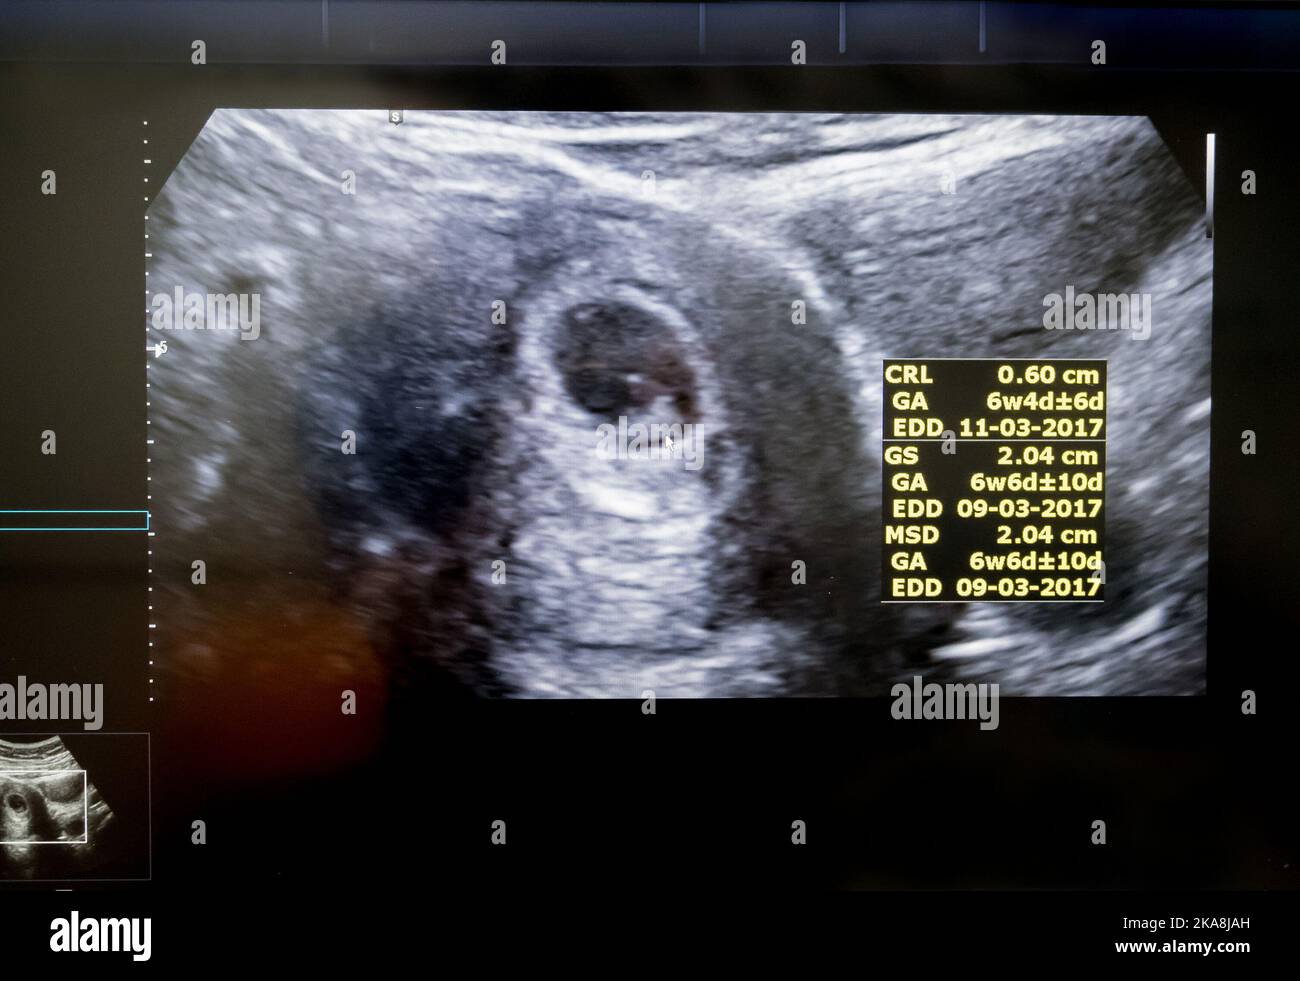

Früher Ultraschall (ca. 5-6 Wochen): Hier sieht man meistens nur die Fruchthöhle. Das ist wie eine kleine Blase, in der sich der Embryo entwickelt. Manchmal kann man schon den Dottersack erkennen, der den Embryo in den ersten Wochen ernährt. Der Embryo selbst ist oft noch zu klein.

Ultraschall in der 7-8. Woche: Jetzt wird es spannender! In dieser Zeit ist der Embryo meistens deutlich zu sehen. Du kannst jetzt vielleicht einen kleinen Punkt erkennen, der dein Baby ist. Oft kann man jetzt auch den Herzschlag sehen und hören. Das ist ein sehr emotionaler Moment!